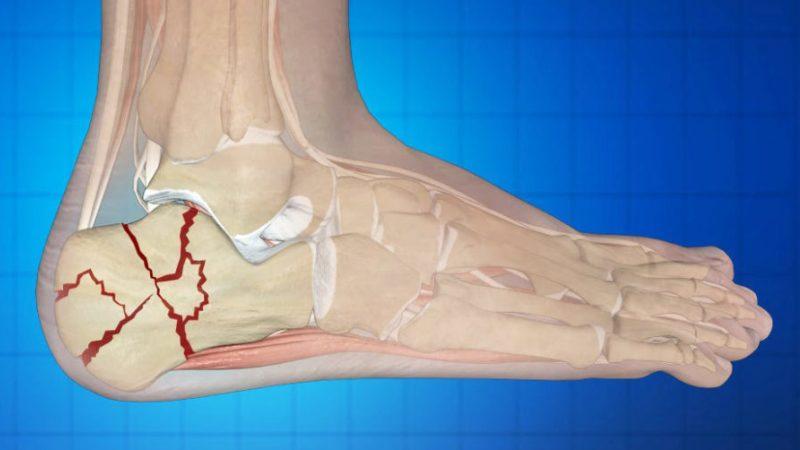

Например, оскольчатый перелом кисти может стать причиной повреждения нервного пучка, что впоследствии проявится в параличе кисти и пальцев, а перелом большеберцовой кости повлечет за собой ухудшение кровообращения в стопе.